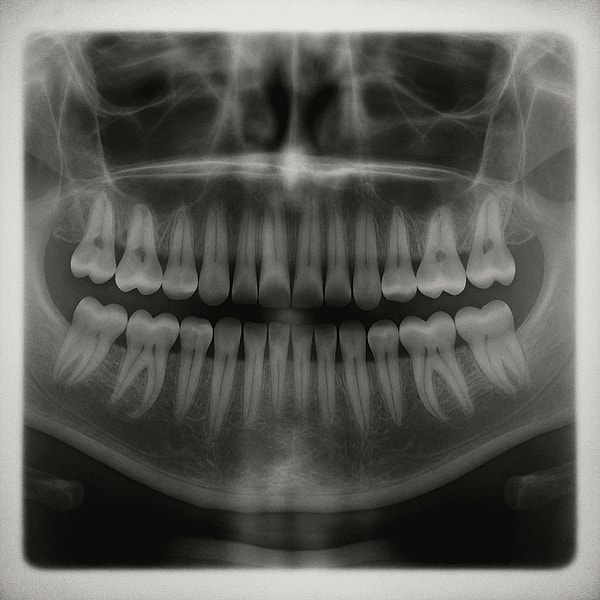

It is also believed that the foundations of a third set of teeth already exist in people's mouth structure. This situation is also observed in cases of hyperdontia, where extra teeth grow. Scientists believe that these dormant tooth buds can be genetically reactivated.